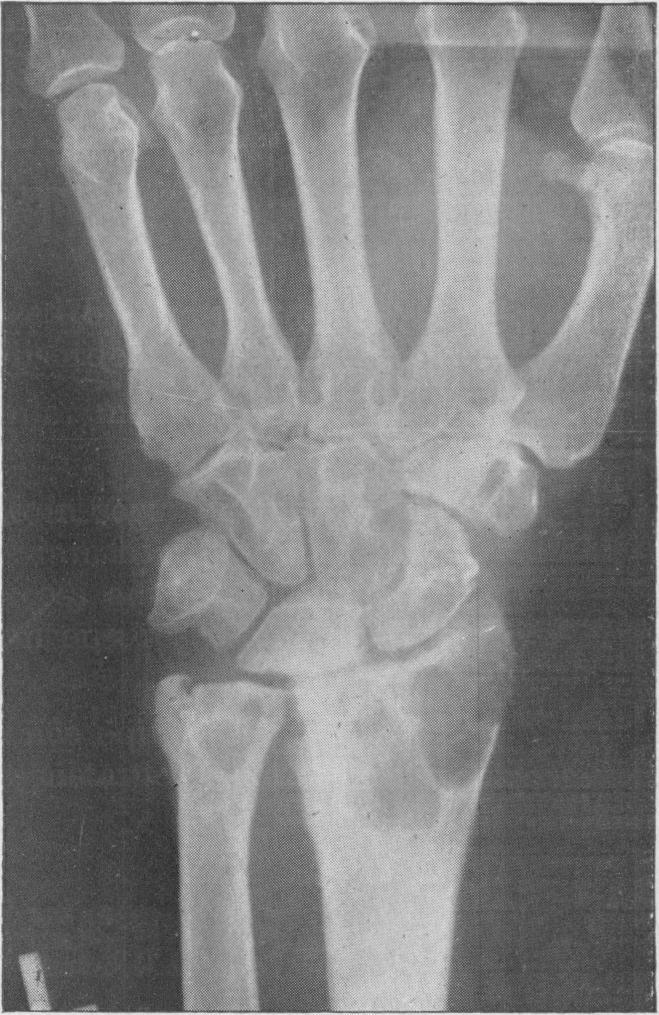

Multiple cysts of bones of extremities of unknown aetiology.